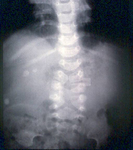

Radiografia abdominal exibindo padrão de gases com sinal da dupla bolha consistente com atresia duodenal

Do acervo de Dr. KuoJen Tsao; usado com permissão